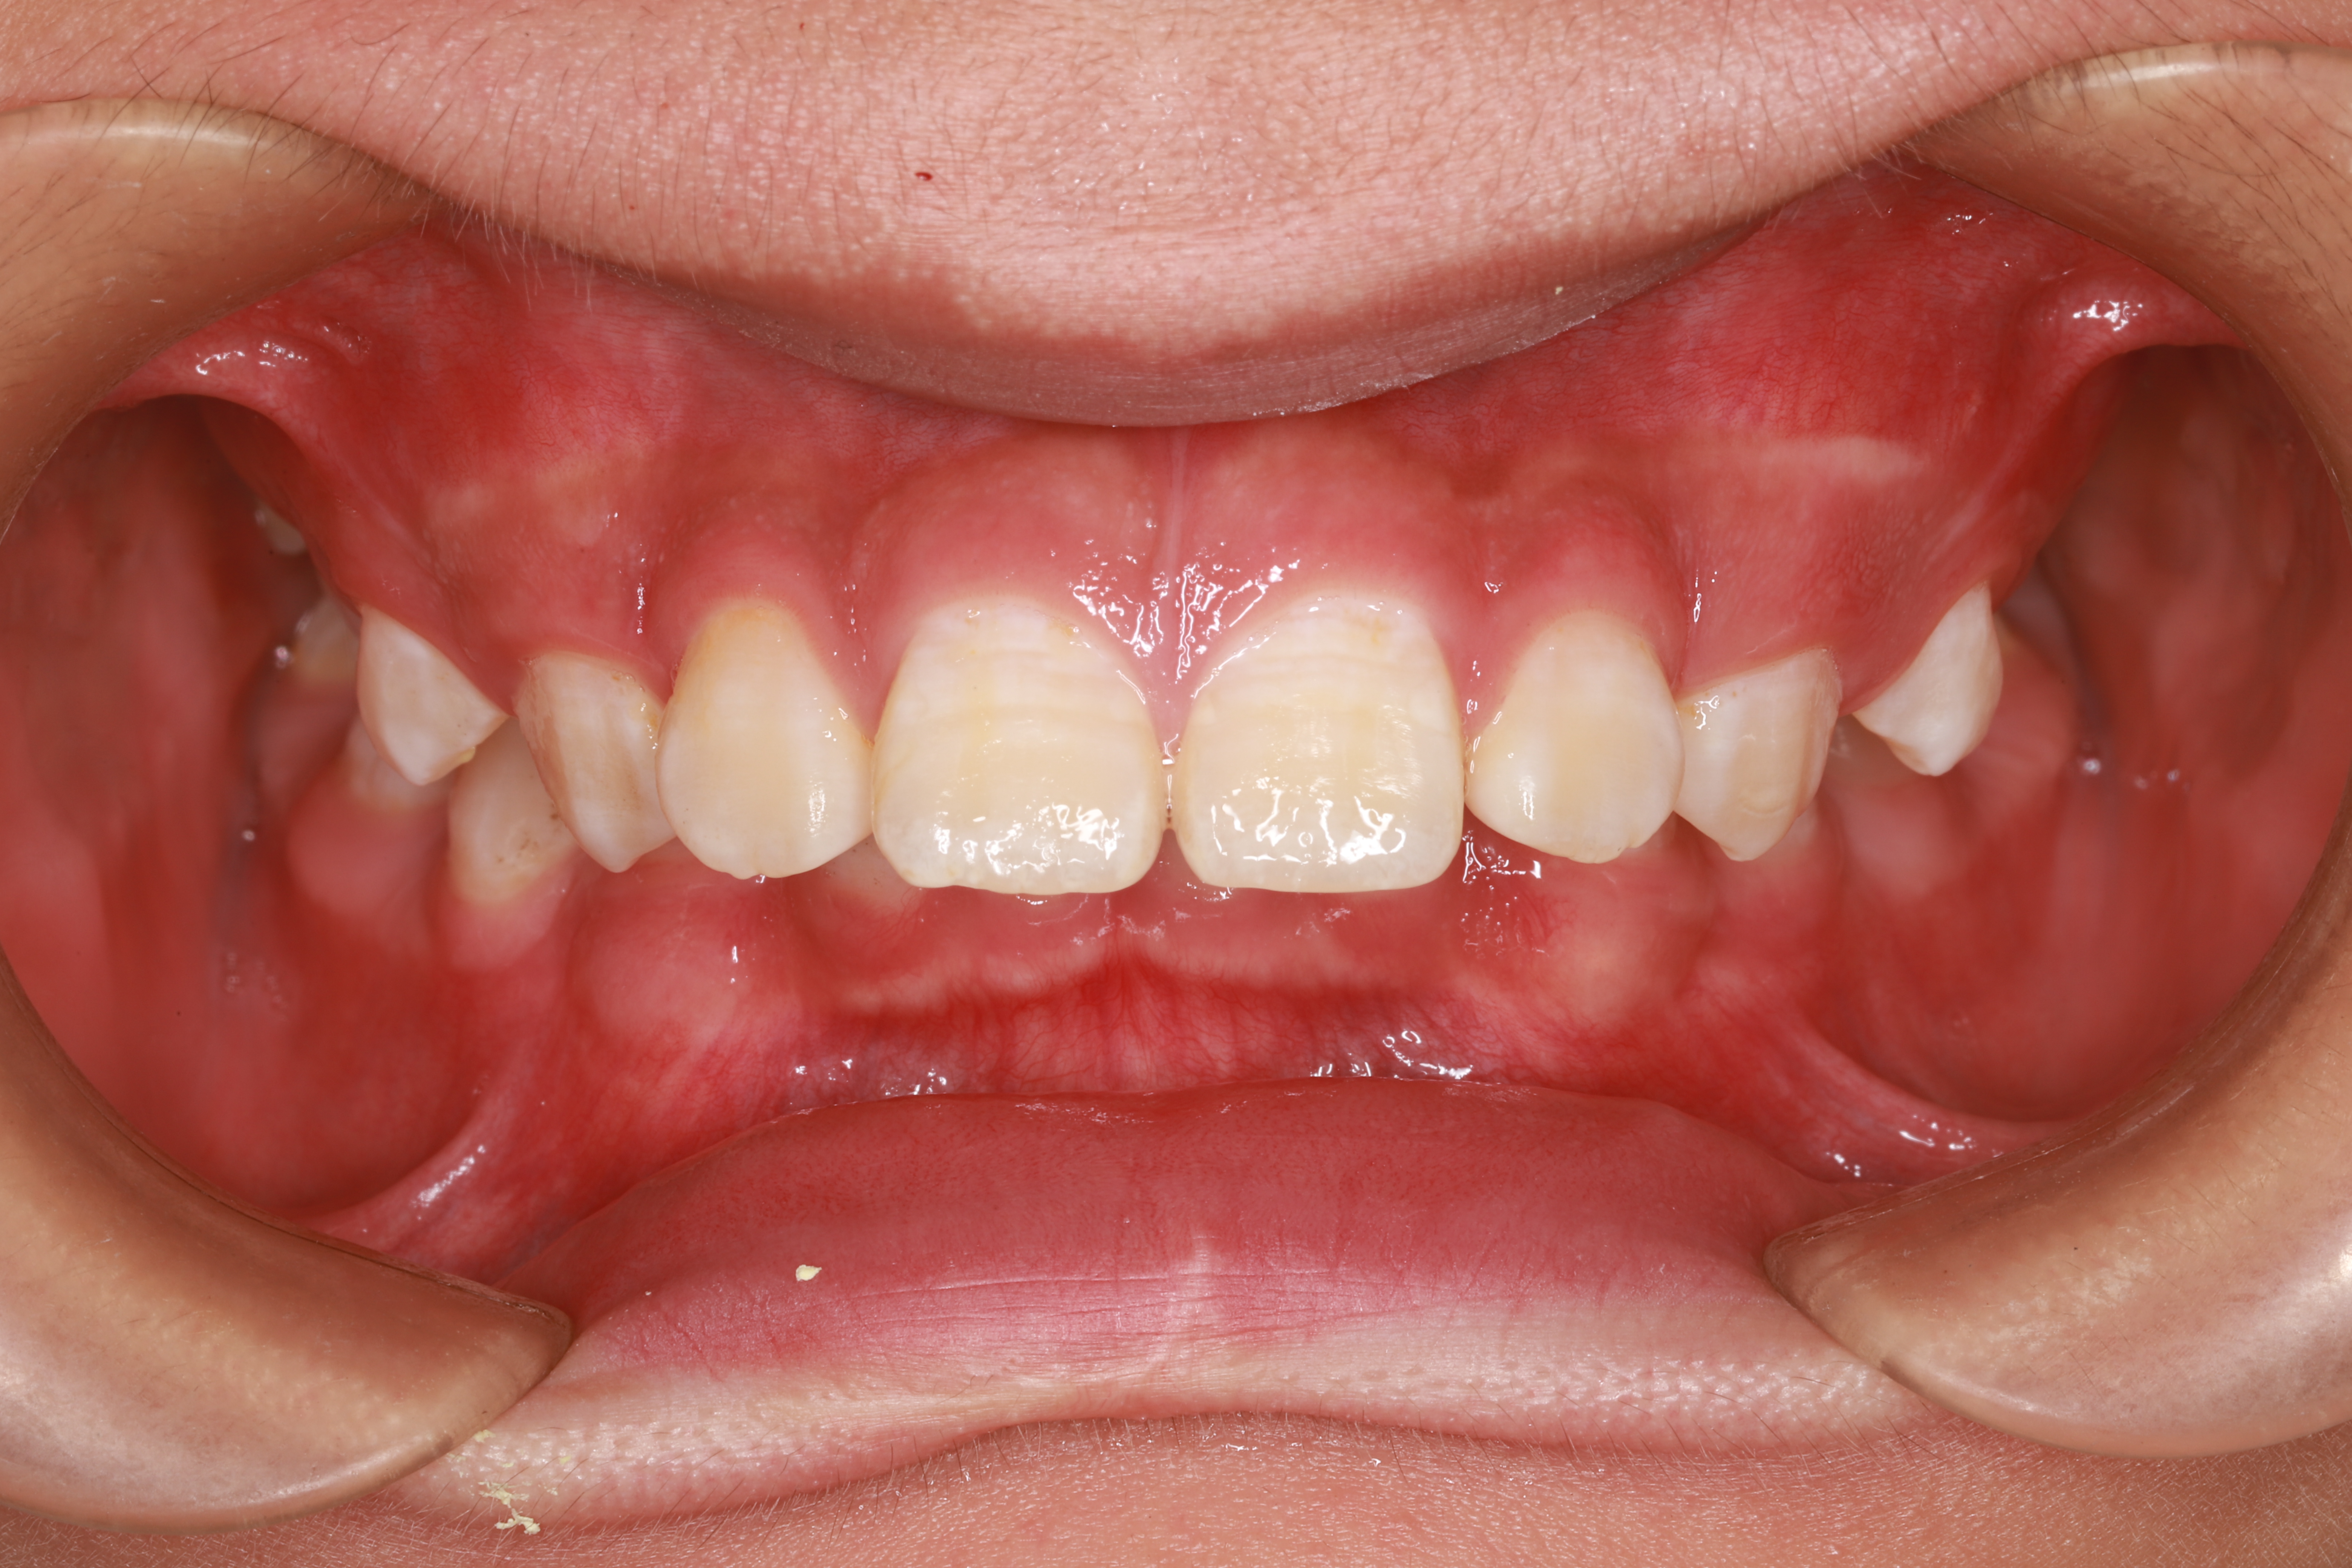

在回答这个问题之前,请看看下面几张图片。

关于儿童牙齿矫正那些事(图1)

反颌